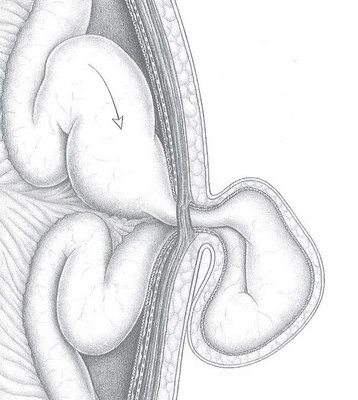

Bei jedem Bruch mit einer Bruchlücke größer als 2 bis 3 Zentimeter wird die Bauchdecke mit einem Kunststoffnetz verstärkt. Denn bei alleinigem Nahtverschluss der Bruchlücke ist die Rezidivgefahr (> 30 Prozent Rückfälle) sehr hoch. Wenn ein Netz implantiert wird, kann die Rezidivrate auf circa 5 Prozent gesenkt werden. Die Operationsmethode ist entweder offen oder laparoskopisch. Prinzipiell muss nicht nur die gesamte Narbe mit dem Netz verstärkt werden, sondern das Netz muss auch sämtliche Lücken um mindestens 3 bis 5 Zentimeter überlappen. Nur so kann ein erneuter Rückfall weitestgehend vermieden werden. Eine aufwendige Operation erfolgt in Abhängigkeit von Größe der Narbe und Größe des Bruchs.

Das Netz kann offen oder in minimal-invasiver Technik eingebracht werden. Der Vorteil der offenen Bauchdeckenrekonstruktion ist, dass damit auch sehr große Bauchwandbrüche sicher verschlossen werden können. Nachteilig bei der offenen Operation ist, dass hier ein großer Schnitt erforderlich ist mit entsprechender Traumatisierung der Bauchdecke und großer Wundfläche. Die Gefahr steigt, dass Wundheilungsstörungen und Flüssigkeitsansammlungen entstehen. Der Behandlungsverlauf kann dadurch verlängert werden. Der Vorteil der Laparoskopie sind geringere Schmerzen und ein kürzerer Krankenhausaufenthalt. Außerdem treten nur sehr selten Hämatome, Seromen (Flüssigkeitsansammlungen) oder Wundheilungsstörungen auf. Nachteilig kann sein, dass nicht selten ausgedehnte Verwachsungen im Bauchraum zu lösen sind. Dabei besteht ein gewisses Risiko, dass der Darm verletzt wird. Und: Da bei dieser Operationsmethode ein direkter Kontakt zwischen Netz und Darm nicht zu umgehen ist, muss ein spezielles Netz implantiert werden, das Verwachsungen zum Darm mit möglichen nachteiligen Folgen für die Darmpassage ausschließt. Ein derartiges Netz ist ausgesprochen teuer.